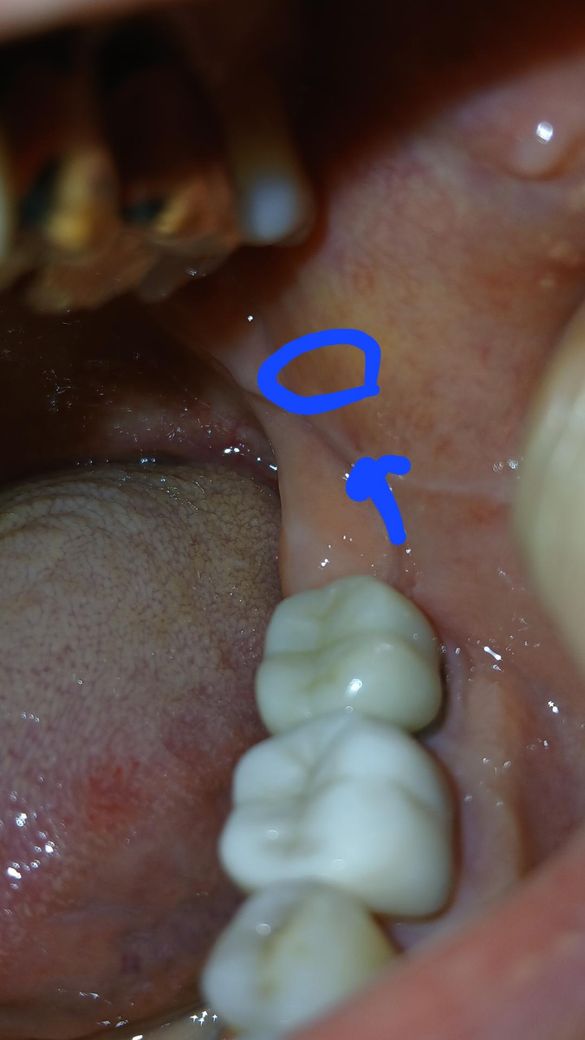

입안 볼점막에 생긴붉은색반점?같은

처음사진은 일주일전사진이고

두번째사진은 오늘찍은사진인데

붉은원같이 생겻다가. 오늘사진은

많이 색이옅어진것같았는데

저녁때다시보니 비슷한붉은기운이 두번째사진동그라미부분에 2개

더생겼어요

혹시 볼점막에 생긴암같은건지

걱정됩니다

이비인후과가서 6일전에물어보니 별거아니니까

신경쓰지말라네요

입안들여다고 손가락으로

자꾸만져서 2개가 더생긴걸까요?